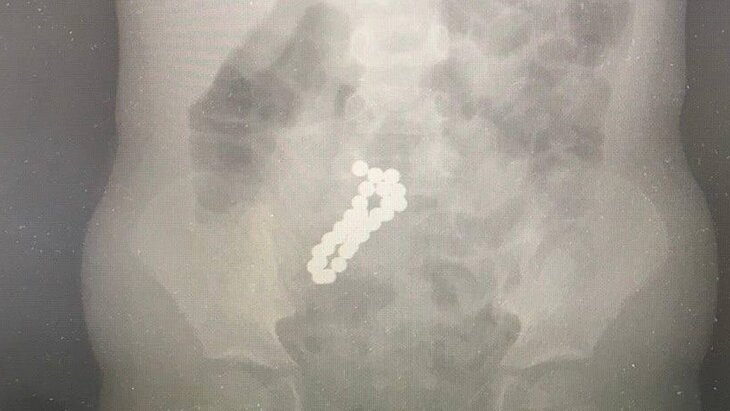

По итогам обследования врачи обнаружили в тонком кишечнике ребенка большое количество инородных тел диаметром по 10 миллиметров каждый. Выяснилось, что девочка проглотила 30 магнитных шариков.

В ходе лапароскопической операции хирурги успешно извлекли все металлические предметы через крошечные проколы. После выполненной процедуры маленькая пациентка быстро пошла на поправку.